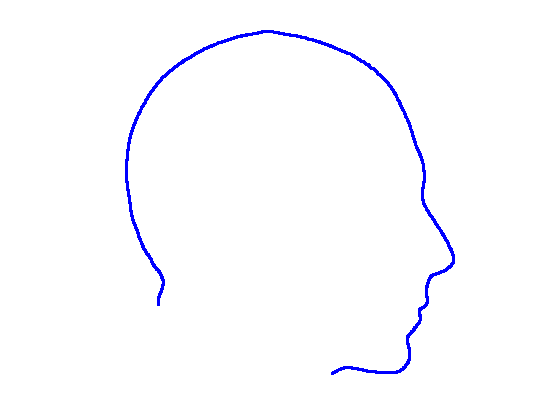

For each of the three segments, we determine the range of gradients on that segment by simple differencing between consecutive points. Each segment is rotated into a 2D frame such that maximum absolute values of positive and negative gradients are equal. Cubic spline contours are fitted to the three profiles and the head profile contour is reconstructed using the three individual cubic splines. Fig. 14 show examples of these.

|